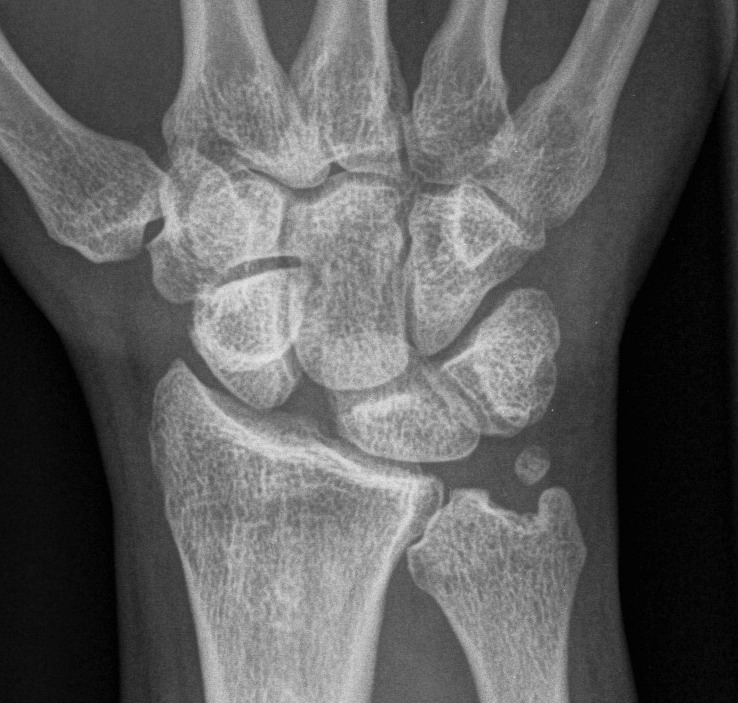

AP

Terry Thomas sign

- increased scapholunate interval

- > 3 mm compared with other side

Cortical Ring sign

- end-on view of cortex of distal pole of scaphoid

Scaphoid shortened

- due to palmar flexion

Look for signs of SLAC wrist

- degenerative changes of scaphoid fossa with relative sparing lunate fossa

- indicates long standing